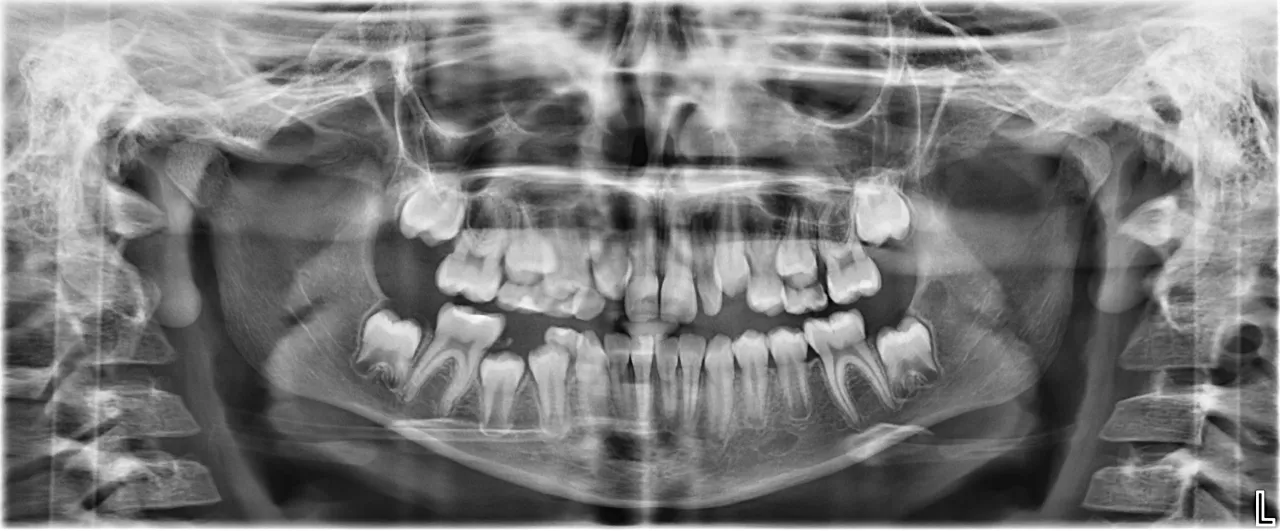

Osteoporoza: Czy zdjęcie rentgenowskie zębów może zdradzić stan Twoich kości?

Osteoporoza, czyli choroba charakteryzująca się zmniejszoną gęstością kości, nie dotyczy tylko kręgosłupa czy kości biodrowych. Ma również wpływ na kości szczęki i żuchwy. Badanie pantomograficzne, czyli panoramiczne zdjęcie rentgenowskie jamy ustnej, które często wykonujemy w gabinecie, może ujawnić zmniejszoną gęstość kości w tych obszarach. Chociaż nie jest to narzędzie do diagnozowania osteoporozy, może być wczesnym sygnałem ostrzegawczym, szczególnie u kobiet po menopauzie, które są w grupie ryzyka. Jeśli zauważam takie zmiany, zawsze sugeruję pacjentowi konsultację z lekarzem w celu dalszej diagnostyki i ewentualnego leczenia. To kolejny przykład, jak stomatologia może być integralną częścią wczesnej diagnostyki chorób ogólnoustrojowych.

Cyfrowe RTG i tomografia CBCT: Precyzyjny obraz bez dużej dawki promieniowania

Radiologia cyfrowa zrewolucjonizowała diagnostykę stomatologiczną. Dzięki cyfrowym zdjęciom rentgenowskim (RVG) mogę uzyskać precyzyjny obraz struktur zęba i kości przy minimalnej dawce promieniowania, znacznie niższej niż w przypadku tradycyjnych klisz. Obrazy są natychmiast dostępne na ekranie, co przyspiesza diagnostykę i pozwala mi na dokładne powiększenie i analizę. Jeszcze bardziej zaawansowaną technologią jest tomografia komputerowa wiązki stożkowej (CBCT). To trójwymiarowe badanie, które dostarcza niezwykle szczegółowych informacji o anatomii kości, położeniu zębów, nerwów i zatok. CBCT jest nieocenione w precyzyjnej diagnostyce, zwłaszcza w planowaniu leczenia implantologicznego, skomplikowanych zabiegów endodontycznych (leczenie kanałowe) czy ekstrakcji zębów zatrzymanych. Dzięki tym technologiom mogę postawić jeszcze dokładniejszą diagnozę i zaplanować leczenie z najwyższą precyzją, co przekłada się na lepsze i bezpieczniejsze wyniki dla Ciebie.